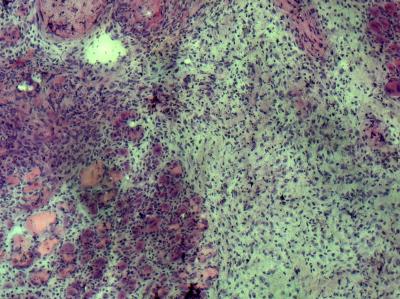

As expected, the researchers found that muscle tissue in the young mice easily replaced damaged cells with new, healthy cells. In contrast, the areas of damaged muscle in the control group of old mice were characterized by fibroblasts and scar tissue.

However, muscles in the old mice whose stem cell "aging pathway" had been dampened showed levels of cellular regeneration that were comparable to their much younger peers, and that were 3 to 4 times greater than those of the group of "untreated" old mice.